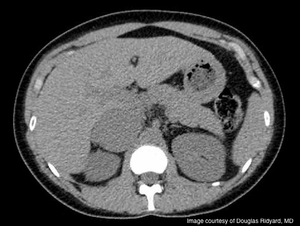

An 18-year-old previously healthy collegiate athlete presented to the emergency room with a rapid weight gain of 20 pounds during the previous 2 months. She complained of significant fatigue and irregular menstrual periods.